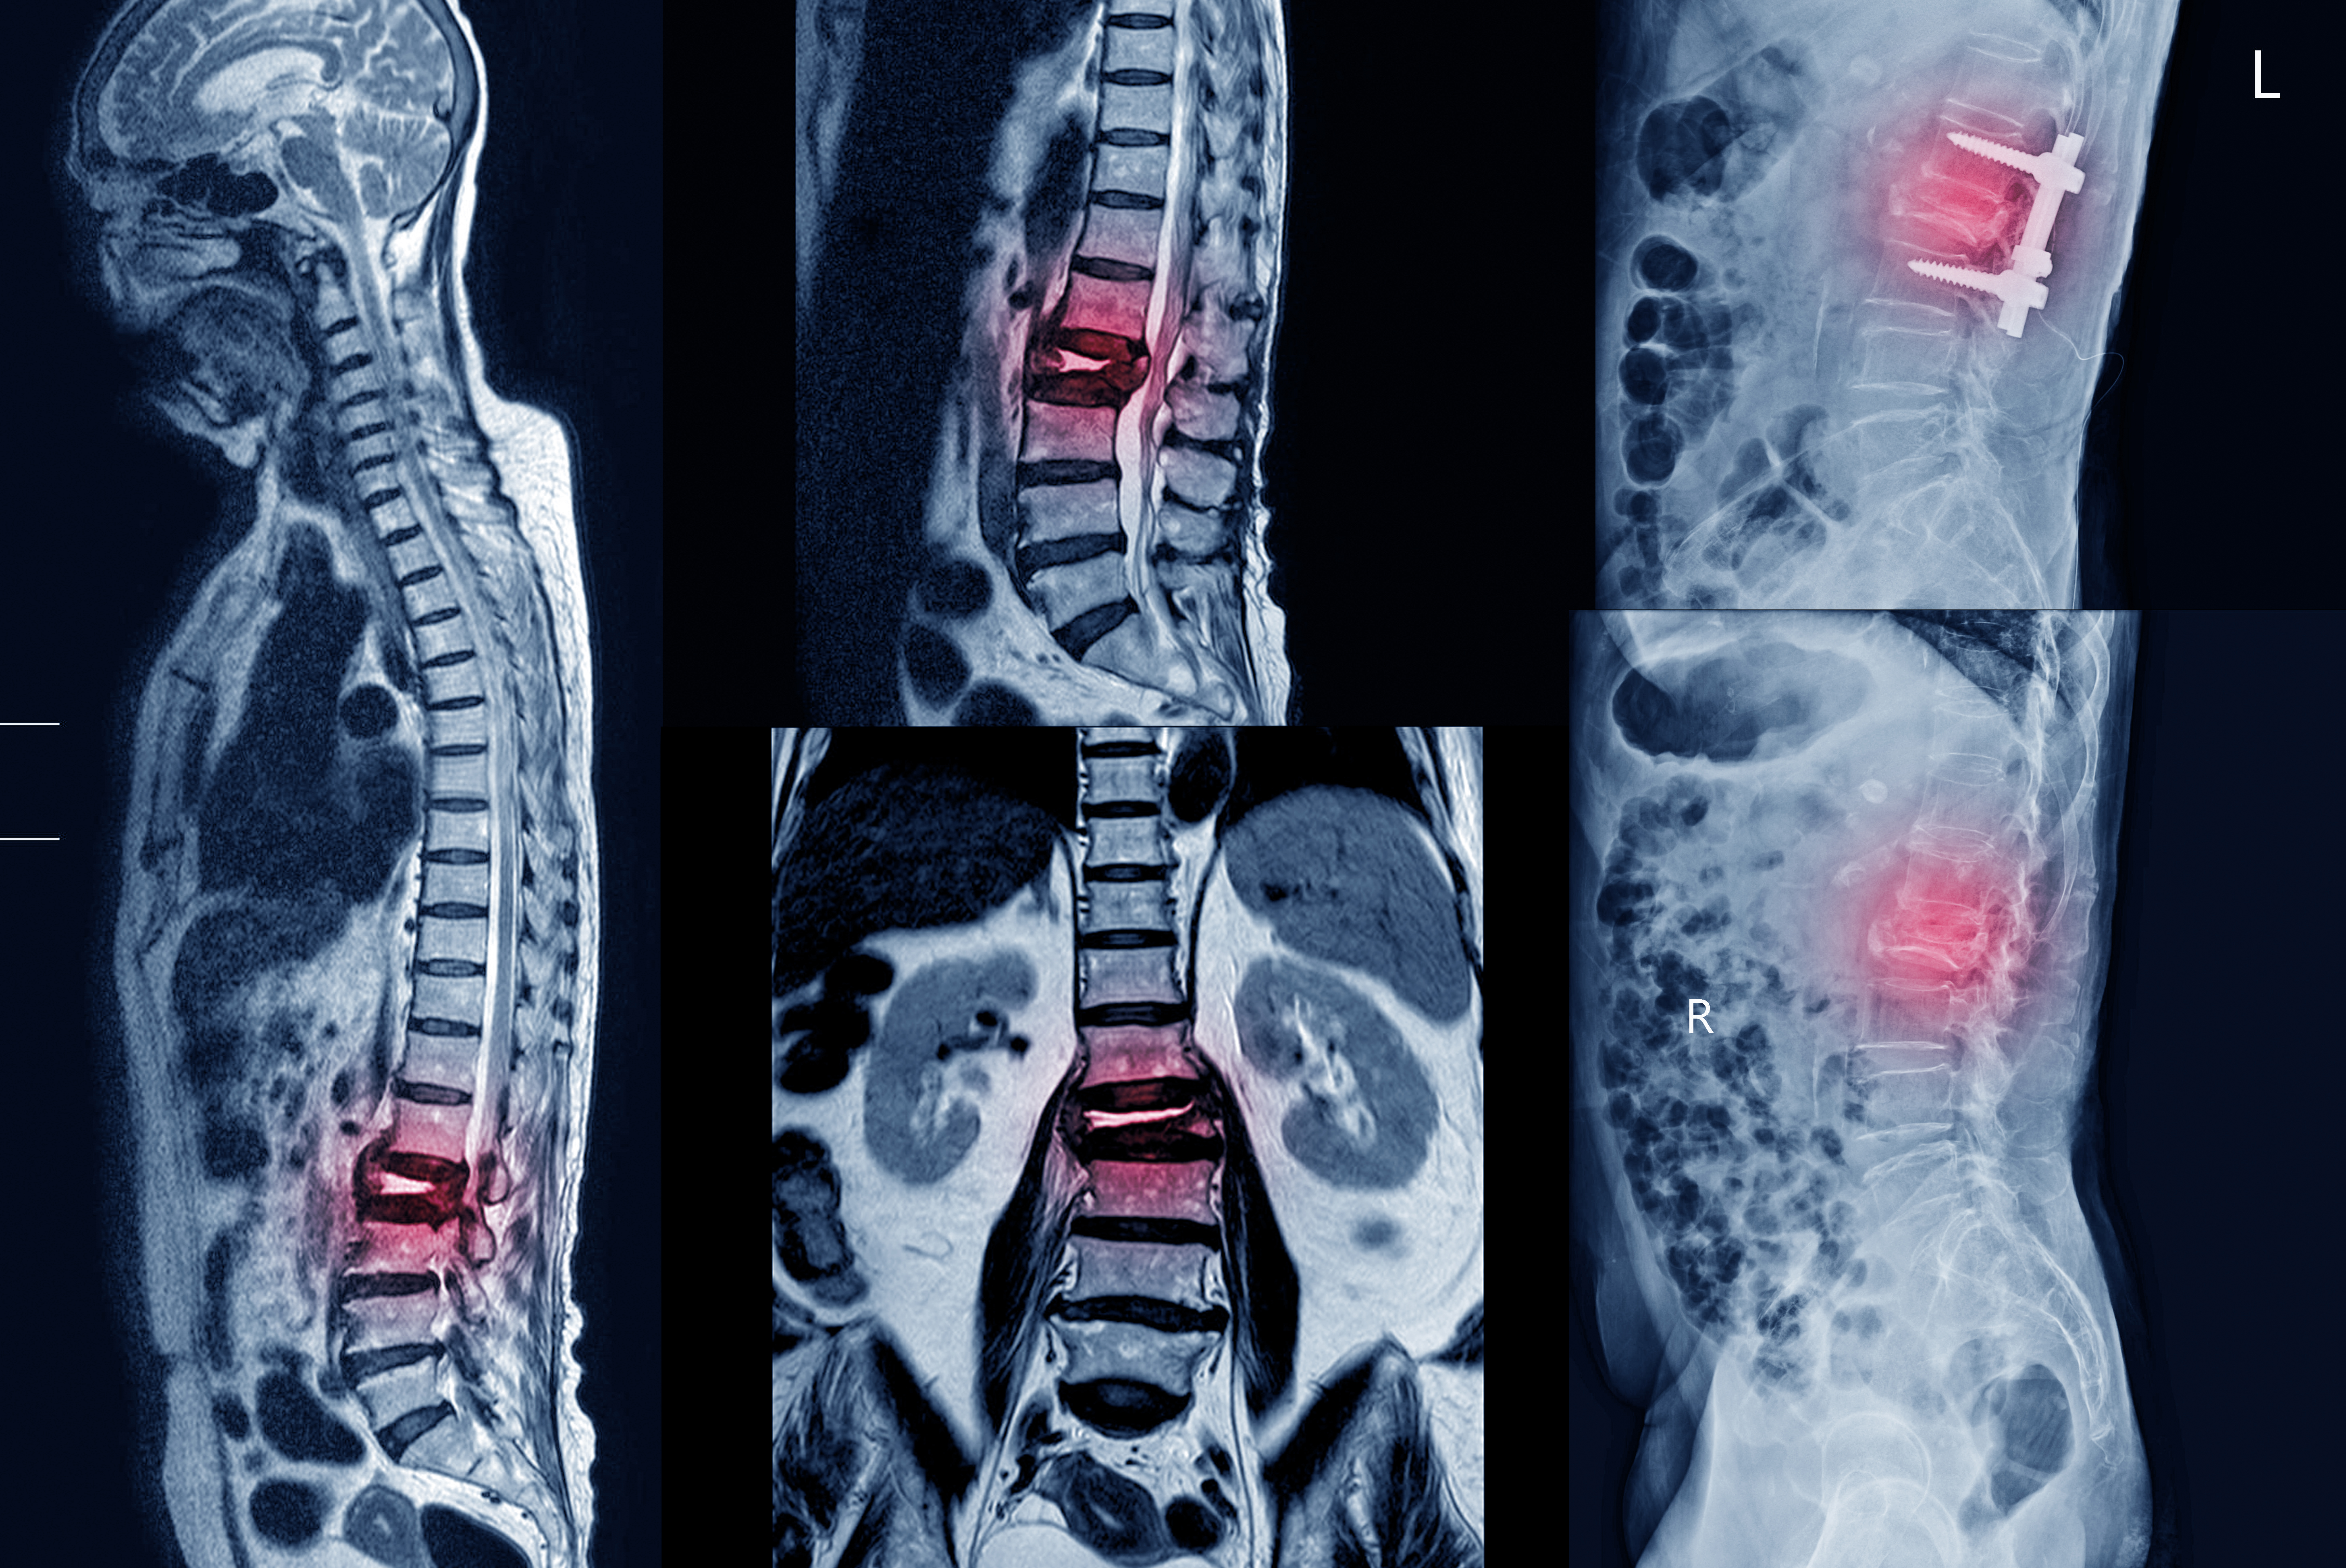

神經外科與神經科(內科)不同,是外科的其中一門專科,

神經外科主要以外科手術方法來治療神經系統,

包括腦部、脊柱、神經末梢、及腦血管系統。

神經外科主要治療的病變包括:

- 脊髓腫瘤

- 椎管狹窄